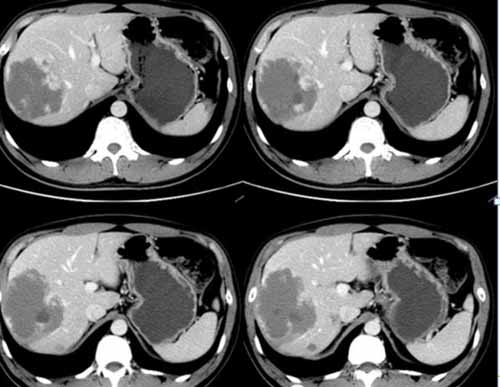

我們來看一個典型病例:

(術前右肝肝包膜下巨大血管瘤)